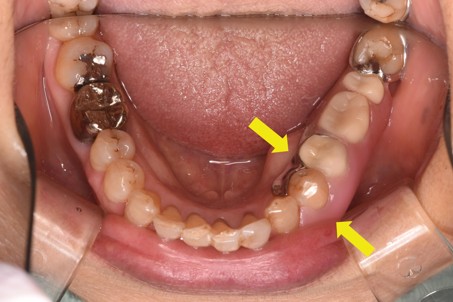

治療前

左下奥歯に歯が無い状態で、入れ歯の支えになる歯が強い咬み合わせで負担がかかり、揺れていました。 |

まずは咬み合わせの調整を行い、入れ歯の支えになる歯の動揺を減らしてから入れ歯の作製を始めました。 |